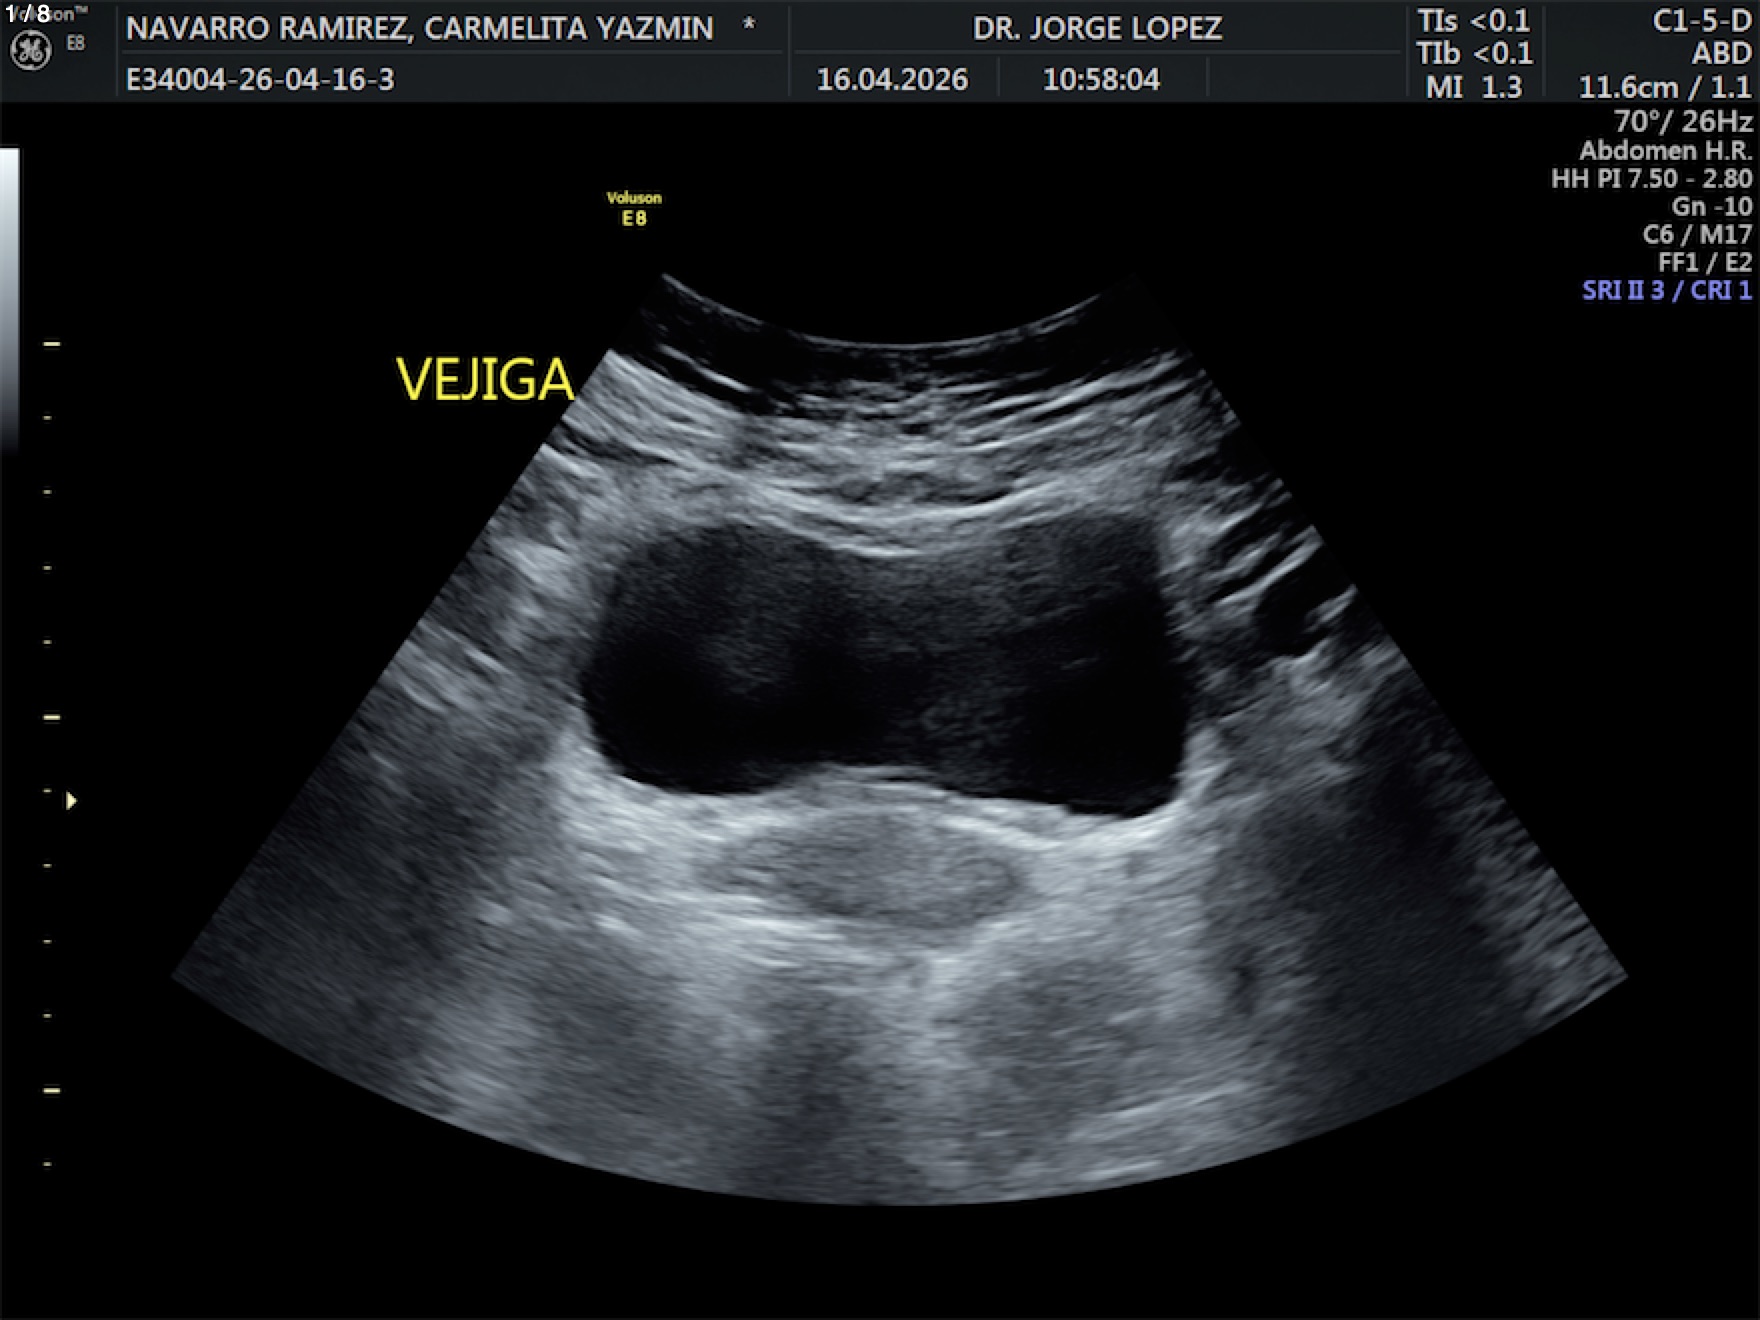

Navarro Ramirez Carmelita Yazmin - Unnamed